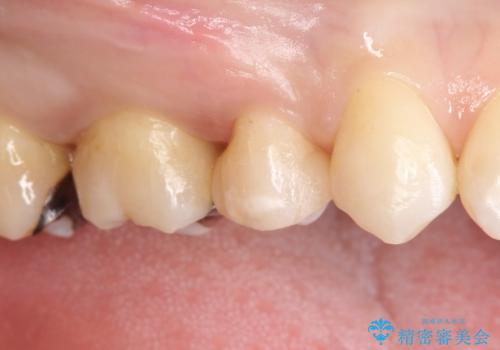

笑ったら銀歯が見える。 セラミックインレーによる治療

- 笑ったときに銀の詰め物が見えることを主訴に来院されました。

セラミックインレーにて修復を行いました。

保険治療で使える材料には制限があり、見た目だけでなく精度でも劣ります。当院でのセラミックインレーは歯とのつなぎ目を拡大鏡で確認して精度高く仕上げるため、むし歯のリスクを限りなく少なくできるよう治療します。